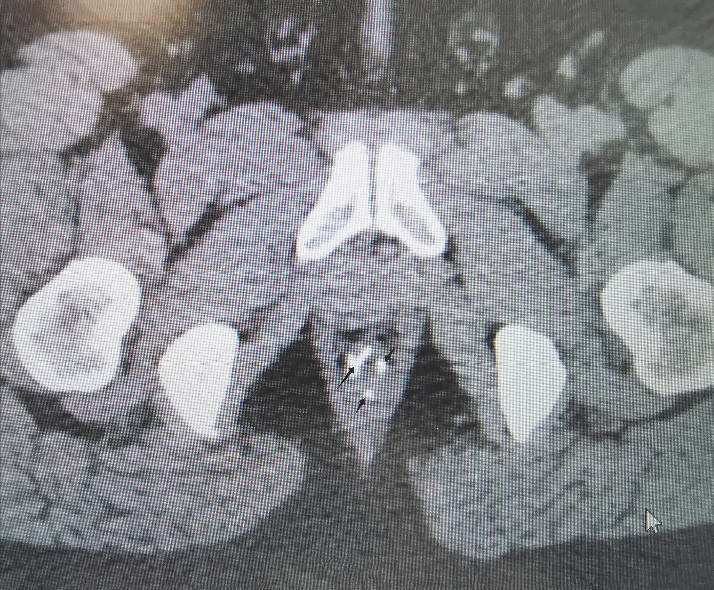

(7)放射影像表现:内痔的组织结构包括黏膜层、黏膜下层、毛细血管网,及更深层次的基质结构,包括肌肉、结缔组织,其中含有血管结构(大部分为扩张的静脉),这部分结构在磁共振影像中呈现出黏膜层的透亮影(图 2—21黑箭头所指区域)。

图 2—21 磁共振下痔的表现

图 2—25 黑色箭头所指为残钉在CT中的显影